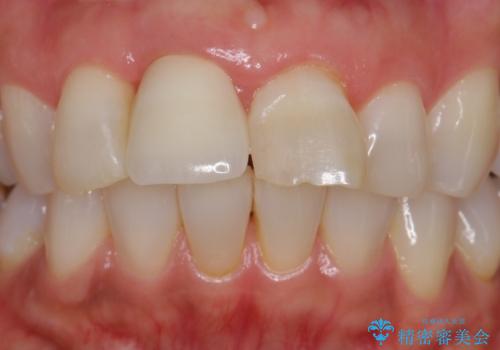

ぶつけて埋まってしまった歯は、場合によって矯正治療で引っ張り出すことで保存することができます。

今回は歯の神経が死んでしまっていたため、根管治療後に被せ物を装着して見た目の綺麗さを回復しました。